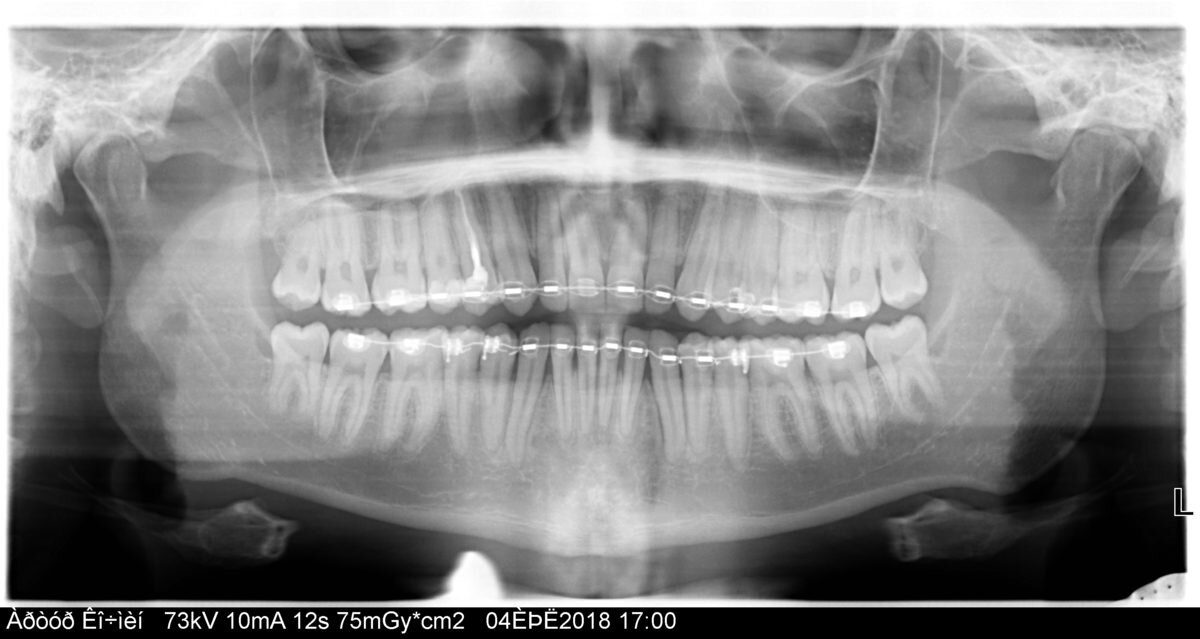

b) Ортопантомограмма (ОПТГ) или иначе панорамный снимок

Применяется, на сегодняшний день, в основном для первичной консультации( определить какие есть зубы, какие пролечены, а какие нет) т.е показывают общую картину.